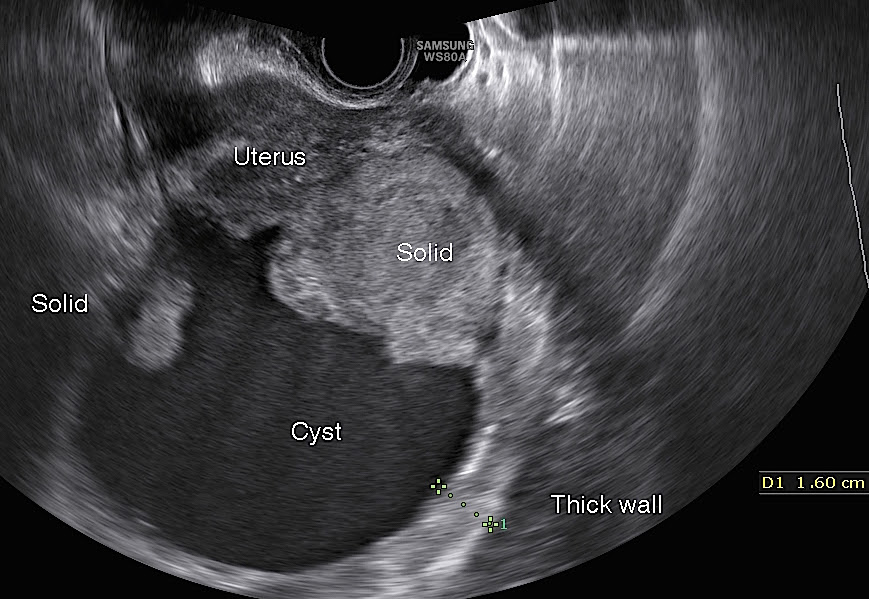

The diagnosis of ovarian cysts typically involves a combination of medical history, physical examination, and imaging studies. The primary diagnostic tools include:

- Pelvic ultrasound: This non-invasive imaging technique is the most common method for visualizing ovarian cysts

How accurate is ultrasound in detecting ovarian cysts? Ultrasound is highly effective in identifying ovarian cysts, with a sensitivity of up to 90%. However, its accuracy can vary depending on factors such as cyst size and location.

Ovarian cysts can be seen on an ultrasound. They are often discovered by chance, for instance when doing an ultrasound scan of the ovaries. Some cysts can be felt too.

As for how an ovarian cyst is diagnosed, in some cases a professional doctor can check for the presence of the disease even with his bare hands, using a manual examination. Nevertheless, in order to make an accurate diagnosis, a professional specialist must check the tests, clarify the presence of signs that characterize the disease of the cysts of both ovaries and conduct an ultrasound scan. It is an ultrasound study for women who have an ovarian cyst that better than any analysis or symptom allows them to determine the presence of a growth.

Ultrasound without any errors quickly and professionally locates ovarian cysts and, better than any blood test, gives an accurate diagnosis. So, with the help of ultrasound examination and the professionalism of a doctor, one can find out not only the localization of the disease, which is shown on the screen as a dark spot.

You can see the size, suggest what type the cyst belongs to. In addition, such a modern analysis makes it possible to understand whether the disease can be cured by traditional drug therapy or whether surgical intervention is necessary.Such analyzes show what is happening inside the female body, how the disease is diagnosed and what is the best treatment to apply.